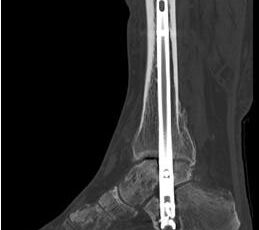

Durch die Fusion des oberen und unteren Sprunggelenkes soll eine Schmerzfreiheit bei gleichzeitiger Stabilität und Belastbarkeit in den genannten Gelenkabschnitten erreicht werden. Die Mobilität des Patienten bleibt damit gewährleistet. Durch Resektion der Gelenkflächen im OSG und im USG kann die Achse im Sprunggelenk korrigiert werden 67. Die Retention erfolgt durch einen von plantar aus eingebrachten Verriegelungsnagel. Orthopädietechnische Schuhzurichtungen oder sogar die Anpassung von orthopädischen Massschuhen sind nach einer Versteifungsoperation im OSG und USG häufig sinnvoll.

Von plantar aus nun Incision und Vorschießen eines 3er KDs durch Calcaneus, Talus bis in den Tibiaschaft hinein. BV-Kontrolle in beiden Ebenen. Bei korrekter Lage nun Eröffnungsbohrung. Wechsel auf einen Draht mit Olive. BV-Kontrolle in beiden Ebenen. Über den stumpfen Draht nun Aufbohren mit flexiblen Bohrern. Der letzte Bohrerdurchmesser sollte den Durchmesser des Arthrodesenagels um mindestens einen Millimeter übersteigen.

Implantation des Nagels und BV-Kontrolle (Video 5). Schließlich erfolgt die Verriegelung des Nagels über entsprechende Zielvorrichtungen. Bei einigen Nageltypen gibt es nageleigene Kompressionsmechanismen, die eine zusätzliche Drucksteigerung im Bereich der Arthrodeseflächen des ehemaligen oberen und unteren Sprunggelenkes erlauben (Video 6). Die abschließende BV-Kontrolle in beiden Ebenen sollte eine regelrechte Stellung der Arthrodese mit 90° - Stellung im Rückfuß, in der anderen Ebene mit einem Rückfußvalgus von ungefähr 5° zeigen.